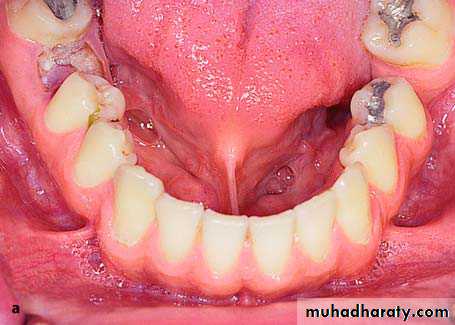

Papillary Hyperplasia of the Palate

Papillary hyperplasia is a rare pathologic condition localized most often in the palate. It usually occurs in edentulous patients who have been wearing dentures for a long time and is possibly due to inflammatory hyperplasia of the mucosa because of chronic local irritation. It also occurs in dentate patient, etiological factors include mechanical and thermal irritation from foods, smoking, etc.

Clinically, these are multifocal hyperplastic nodules of the mucosa of the palate, between which food may accumulate, potentiating the inflammatory reaction.

Treatment is surgical and consists of removal of the lesion with a scalpel or electrosurgical loop.

The traumatized area is covered with a surgical dressing and healing is achieved by secondary intention

preprosthatic surgery